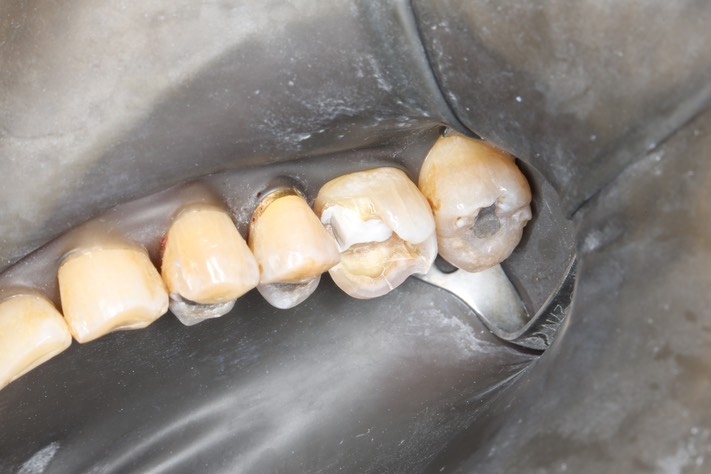

Ted Kanamori #14 buccal view